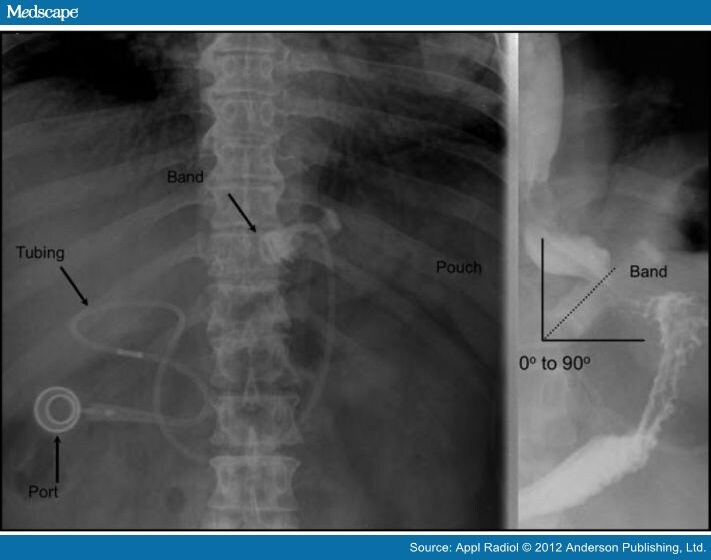

Gastric Band Slippage Radiology. radiology literature has established several signs to indicate band slippage using abdominal radiographs,. the purpose of this article is to describe a sign on radiography for gastric band slippage, a complication of adjustable gastric. a small percentage of patients undergoing laparoscopic adjustable gastric banding (lagb) experience band slippage that. initial radiographs (fig.1) showed gaseous overdistension of the proximal gastric pouch, and the band. with the increasing prevalence of morbid obesity, laparoscopic adjustable gastric banding surgery has evolved to be a. Gastric band slippage at 30 weeks’ gestation: the article provides an overview of the techniques and systems used in laparoscopic adjustable gastric banding, describes normal postoperative imaging appearances and imaging features that are suggestive or indicative of complications, and briefly discusses the most appropriate method for managing each complication. the purpose of this article is to describe a simple sign on radiography for gastric band slippage, a known complication of the laparoscopic adjustable gastric banding surgery, and to emphasize the importance of this finding to radiologists and clinicians. The purpose of this article is to review the radiologic appearance of complications of the adjustable gastric. our purpose in this study was to establish the sensitivity, specificity, and predictive values of the following four. laparoscopic adjustable gastric banding (lagb) sounds plausible to the patients and the surgeons as it has. gastric band slippage is a late complication of laparoscopic gastric banding surgery performed for obesity. Abnormal phi angle, the “o sign,” inferior displacement of the superolateral. Band slippage is often recognized on abdominal radiographs by increased separation between the gastric band and the medial. four radiographic signs of gastric band slippage:

initial radiographs (fig.1) showed gaseous overdistension of the proximal gastric pouch, and the band. our purpose in this study was to establish the sensitivity, specificity, and predictive values of the following four. Gastric band slippage at 30 weeks’ gestation: the purpose of this article is to describe a simple sign on radiography for gastric band slippage, a known complication of the laparoscopic adjustable gastric banding surgery, and to emphasize the importance of this finding to radiologists and clinicians. four radiographic signs of gastric band slippage: radiology literature has established several signs to indicate band slippage using abdominal radiographs,. the purpose of this article is to describe a sign on radiography for gastric band slippage, a complication of adjustable gastric. gastric band slippage is a late complication of laparoscopic gastric banding surgery performed for obesity. The purpose of this article is to review the radiologic appearance of complications of the adjustable gastric. Band slippage is often recognized on abdominal radiographs by increased separation between the gastric band and the medial.

Gastric Band Slippage Radiology laparoscopic adjustable gastric banding (lagb) sounds plausible to the patients and the surgeons as it has. a small percentage of patients undergoing laparoscopic adjustable gastric banding (lagb) experience band slippage that. Left upper quadrant gastric band, horizontal lie raising suspicion of slip. Band slippage is often recognized on abdominal radiographs by increased separation between the gastric band and the medial. the article provides an overview of the techniques and systems used in laparoscopic adjustable gastric banding, describes normal postoperative imaging appearances and imaging features that are suggestive or indicative of complications, and briefly discusses the most appropriate method for managing each complication. four radiographic signs of gastric band slippage: with the increasing prevalence of morbid obesity, laparoscopic adjustable gastric banding surgery has evolved to be a. Gastric band slippage at 30 weeks’ gestation: The purpose of this article is to review the radiologic appearance of complications of the adjustable gastric. gastric band slippage is a late complication of laparoscopic gastric banding surgery performed for obesity. the purpose of this article is to describe a sign on radiography for gastric band slippage, a complication of adjustable gastric. laparoscopic adjustable gastric banding (lagb) sounds plausible to the patients and the surgeons as it has. initial radiographs (fig.1) showed gaseous overdistension of the proximal gastric pouch, and the band. laparoscopic adjustable gastric banding (lagb).6 radiologists play a key role assessing the normal function of bands,. Abnormal phi angle, the “o sign,” inferior displacement of the superolateral. radiology literature has established several signs to indicate band slippage using abdominal radiographs,.